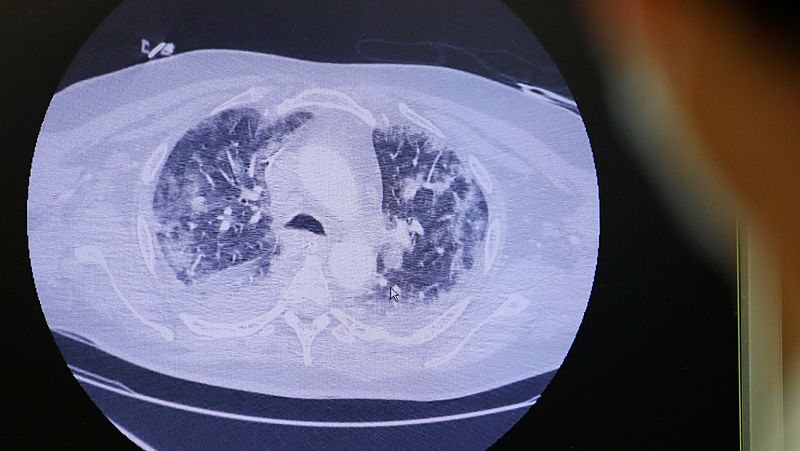

La OMS ha pedido a los países que revisen las historias médicas de pacientes para determinar cuándo empezaron los primeros casos de coronavirus. Ahora en Francia están revisando pruebas de escáner y de otro tipo, que podrían indicar que ya hubo casos de COVID-19 a mediados de noviembre.

Las investigaciones de los científicos galos han determinado que un pescadero de origen argelino que vive en la periferia de París fue, quizás, el primer contagiado por coronavirus. Lo sorprendente es cuando se habría producido este contagio: en diciembre. Un equipo de sanitarios decidieron someter a pruebas específicas a personas que contrajeron supuestas neumonías durante los meses de diciembre y enero y el ya mencionado ciudadano dio positivo. Su esposa trabaja en un puesto de comida en el aeropuerto parisino Charles de Gaulle. Ante esta revelación, la OMS ha pedido al resto de países que investiguen casos similares.

La OMS recomienda analizar neumonías sospechosas de finales de 2019 por si fueran casos de coronavirus

- Considera que el coronavirus pudo estar circulando fuera de China antes de que lo notificara oficialmente